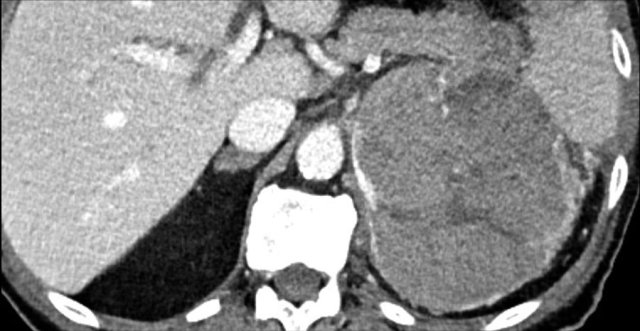

Here a typical example of an adrenocortical carcinoma.

The tumor is bulky and shows heterogeneous enhancement.

Note the 'stellar' central hypodensity.

There is capsular enhancement.

Small adrenocortical carcinomas have less typical features, but also enhance inhomogeneously.

Also note the dystrophic calcifications and areas of necrosis (red arrows).